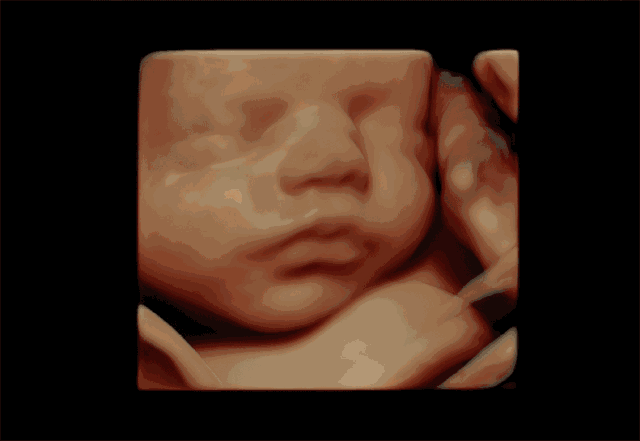

孕婦彩超是一種超聲檢查。除了一般的彩色超聲波功能外,還可以執(zhí)行胎兒頭部和臉部的立體成像。它可以清楚地顯示眼睛、鼻子、嘴巴、腹等狀況,并可以幫助醫(yī)生直接診斷胎兒先天性畸形,包括表面畸形,內(nèi)臟畸形和面部和面部畸形,可以確定胎兒在子宮中的確切位置。

四維彩色多普勒超聲在功能的基礎(chǔ)上還增加了時(shí)間維度參數(shù),并且可以實(shí)時(shí)觀察胎兒動(dòng)態(tài)的運(yùn)動(dòng)圖像,能夠更加清晰的篩查胎兒在子宮內(nèi)的狀態(tài),篩查胎兒是否有異常,提供準(zhǔn)確的科學(xué)依據(jù),及早發(fā)現(xiàn)、及早作出解決方案。

彩超是能夠監(jiān)測(cè)到胎寶寶的健康情況,其中四維彩超除了是準(zhǔn)媽媽和BB的“第一次”見(jiàn)面,還能夠看到ta在肚子里或活潑或文靜的可愛(ài)模樣,從而進(jìn)行重要的排畸檢查,所以也叫胎兒畸形篩查,是孕期特別重要的一次超聲檢查。

飛利浦EPIQ7高端四維彩超擁有高品質(zhì)自動(dòng)成像分析技術(shù),它可以全方位,多角度地觀察宮內(nèi)胎兒的生長(zhǎng)發(fā)育情況,為早期診斷胎兒先天性畸形,如唇裂、脊柱裂、顱腦發(fā)育異常、骨骼發(fā)育異常、心血管畸形等提供準(zhǔn)確的科學(xué)依據(jù)。